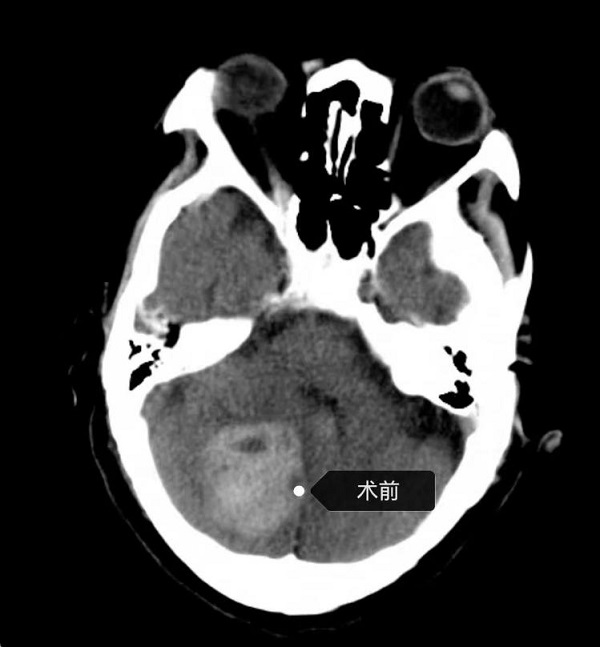

相对于大脑出血,小脑出血往往来的更凶险,小脑出血后很容易诱发枕骨大孔疝压迫脑干导致心跳、呼吸骤停等生命体征不稳定情况发生,进展非常迅速,甚至前一分钟还相谈甚欢,后一分钟就陷入昏迷,因此抢救时间也更...